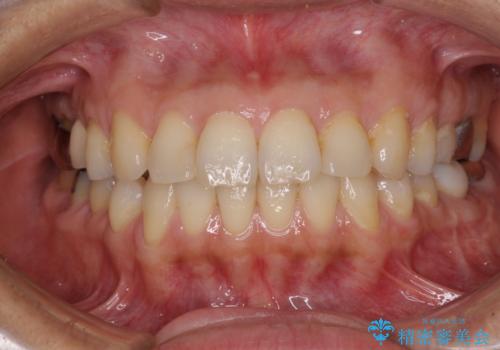

痛む奥歯と矯正の後戻り インビザライン・ライトとセラミック治療

- 高校生の時に行った矯正治療の後戻りと、通院してもなかなか改善しない奥歯の痛みを気にして来院された患者様です。

左下奥歯は、前医より難治性なので抜歯も考えるよう言われたそうですが、一度もラバーダムを用いた根管治療はされていないとのことでした。

まずは左下奥歯の根管治療を行い、痛みが引いたことを確認してから矯正治療を開始しました。

後戻りは軽微であったため、インビザライン・ライトにて歯列を整えました。

矯正治療後には、左下奥歯の症状がないことを確認し、セラミッククラウンにて補綴治療を行うこととしました。